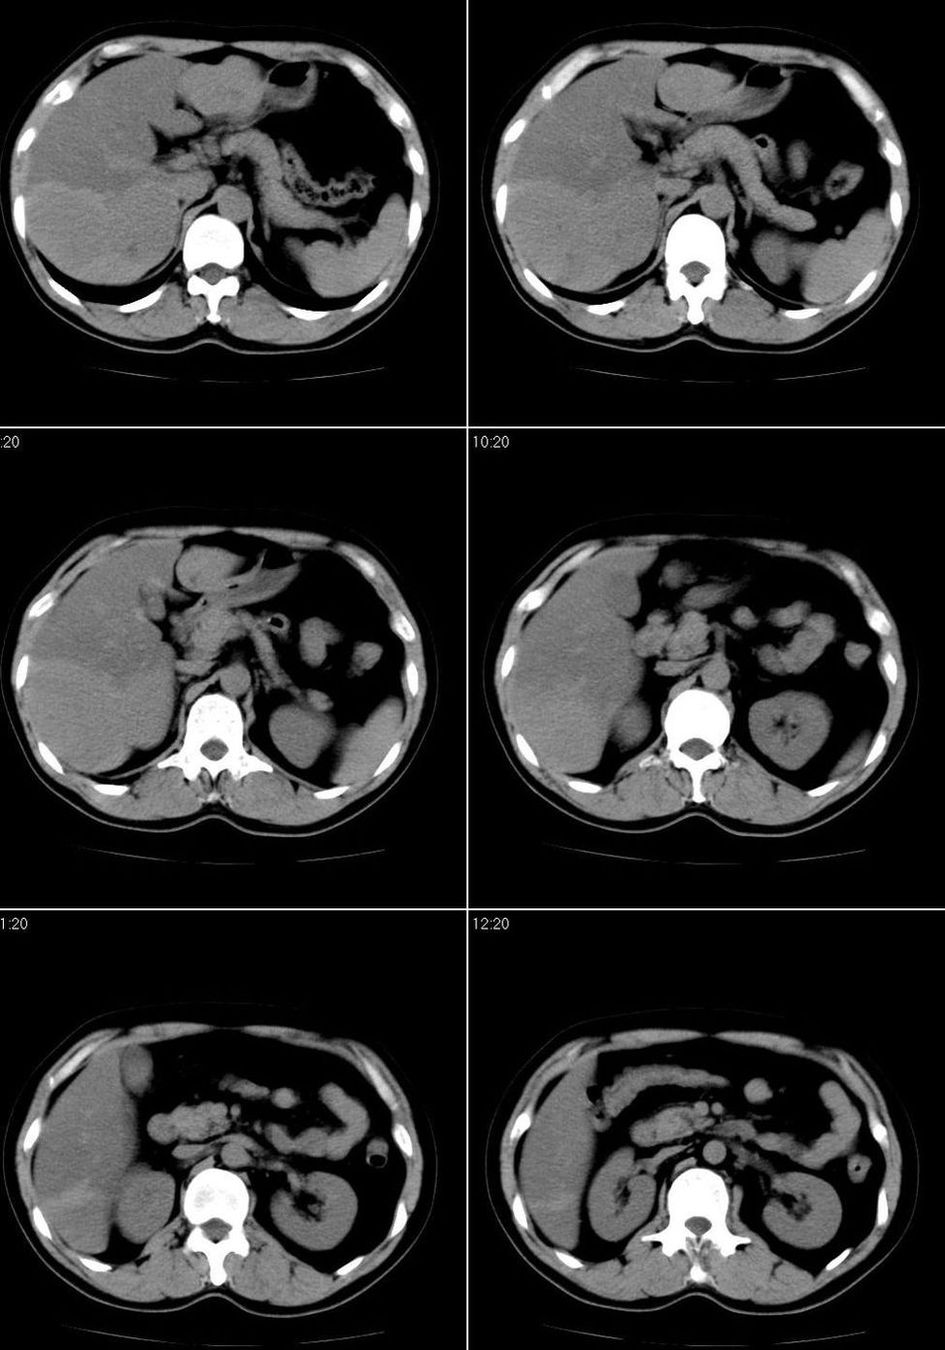

男,43岁。体检发现肝脏病变

结合增强扫描

我觉得肝左叶病变考虑fnh可能性最大。

增强后诊断很明确了,缓慢结节样强化:肝内多发血管瘤

从这个病例可以看出增强ct优势何其重要性和必要性。